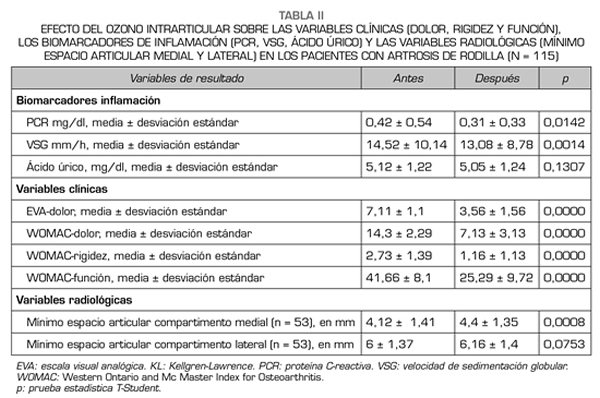

Con respecto a las variables de resultado, los biomarcadores de inflamación PCR y VSG disminuyeron significativamente (p < 0,05) después de la terapia con ozono (O2-O3). La PCR disminuyó de 0,42 ± 0,54 mg/dl a 0,31 ± 0,33 mg/dl (p = 0,0142) (Tabla II). La VSG disminuyó sus valores desde 14,52 ± 10,14 mm/h hasta 13,08 ± 8,78 mm/h (p = 0,0014) (Tabla II). El ácido úrico en suero disminuyó su valor de 5,12 ± 1,22 mg/dl a 5,05 ± 1,24 (p = 0,1307) aunque esa disminución no fue estadísticamente significativa (Tabla II).

Con respecto a la gravedad de los síntomas (dolor, rigidez y función) en la artrosis de la rodilla, medida por las escalas EVA y WOMAC, la terapia con ozono (O2-O3) mejoró significativamente todas y cada una de las variables (p = 0,0000). Antes del tratamiento, el dolor medido por EVA fue de 7,11 ± 1,11 puntos y disminuyó significativamente a 3,56 ± 1,56 puntos (p = 0,0000) (Tabla II). Antes de la intervención, la subescala WOMAC-dolor fue de 14,3 ± 2,29 puntos y disminuyó a 7,13 ± 3,13 puntos (p = 0,0000), la subescala WOMAC-rigidez fue de 2,73 ± 1,39 puntos y disminuyó a 1,16 ± 1,13 puntos (p = 0,0000), la subescala WOMAC-función fue de 41,66 ± 8,1 puntos y mejoró a 25,29 ± 9,72 puntos (p = 0,0000) (Tabla II).

Con respecto a las variables radiológicas, al valorar a 53 de los 115 pacientes que cumplieron un año de seguimiento después del tratamiento con ozono, se observó que el compartimento interno aumento significativamente de 4,12 ± 1,41 mm a 4,4 ± 1,35 mm (p = 0,0008) y el compartimento externo aumentó de 6 ± 1,37 a 6,16 ± 1,4 mm (p = 0,0753) (Tabla II). Se presentan 2 casos clínicos como muestra del cambio radiológico en los compartimentos interno y externo (Figuras 2 y 3).